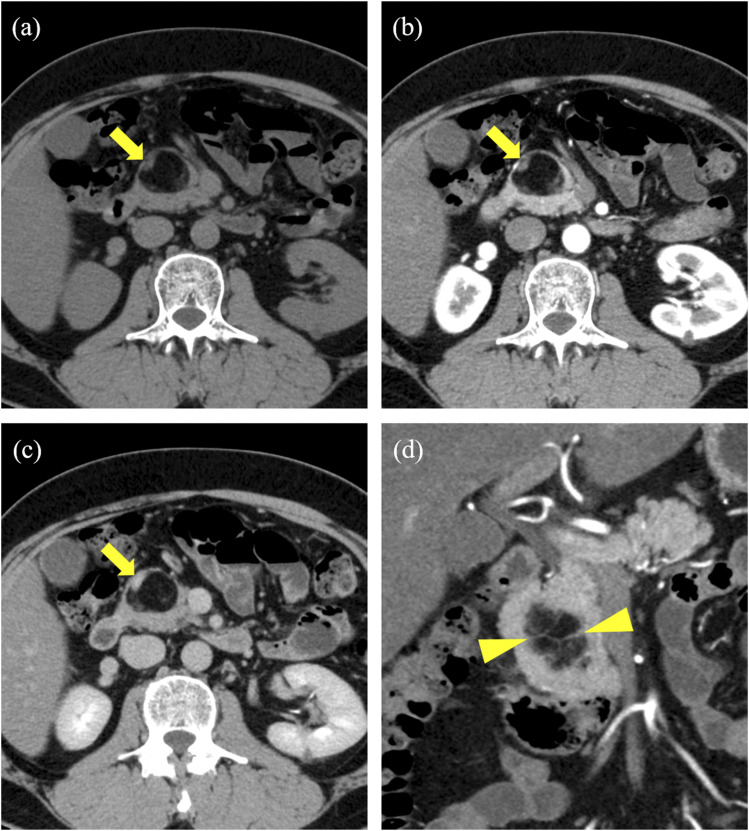

胰腺脂肪瘤性假性肥厚(LPH)是一种罕见疾病,在这种疾病中,胰腺实质被成熟的脂肪组织取代。这是一种特发性疾病,其诊断依据是组织病理学分析。在此,我们报告了一例 50 岁男性患者的病例,他在计算机断层扫描中发现胰腺头部有脂肪瘤肿块,仔细检查后发现是肾肿瘤。我们怀疑是脂肪肉瘤,于是进行了开腹手术。然而,组织学分析却显示为 LPH。LPH的几种成像结果可以实现无创诊断,并有助于临床治疗。

Lipomatous pseudohypertrophy of the pancreas (LPH) is a rare disease in which the pancreatic parenchyma is replaced with mature adipose tissue. It is an idiopathic condition whose diagnosis is made based on histopathological analyses. Herein, we report the case of a 50-year-old male patient with a lipomatous mass in the head of the pancreas on computed tomography for close examination of a renal tumor. We suspected liposarcoma, and laparotomy was performed. However, histological analyses revealed LPH. Several imaging findings of LPH can enable a noninvasive diagnosis and help its clinical approach.